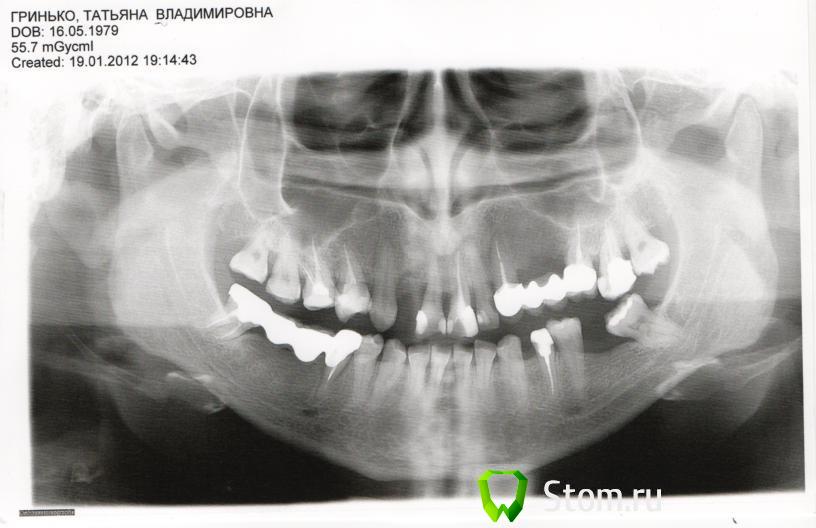

teni79 Опубликовано 26 января, 2012 Поделиться Опубликовано 26 января, 2012 Здравствуйте! Посоветуйте пожалуйста как "исправить" :( ситуацию с выпавшей двойкой??? Одевать все верхние зубы в железо совсем желания нет, но если нет другого выхода то прийдется...Я уже устала перелечивать зубы, каждый раз это все оборачивается все худшими последствиями. И дело ни в клинике, ни стоимости, ни во враче, разные были случаи...Это просто КОШМАР!!!!!!!! :o . Также требуется совет по материалу коронки (моста) (естетика+долговечность+), депульпирование? мосты? или коронки? или имплант? Фото попробую подгузить сейчасhttp://s018.radikal.ru/i517/1201/ad/339b45fb2c01.jpgВсем спасибо, жду ответа не могу принять решение боюсь навредить Ссылка на комментарий

L . O . M . Опубликовано 30 января, 2012 Поделиться Опубликовано 30 января, 2012 Лечение в Вашем случае должно быть комплексным. Сомневаюсь , что уместно составлять план лечения только по выпавшему зубу. Проблем намного больше. И вряд ли здесь можно дать ответ , не видя Вас . По снимку мне видится , что правый верхний первый зуб , возможно , ждёт та же участь , надо смотреть во рту - подвижен ли он . Я рекомендовала бы Вам коллегиальную консультацию и ортопеда , пародонтолога , имплантолога. Ссылка на комментарий